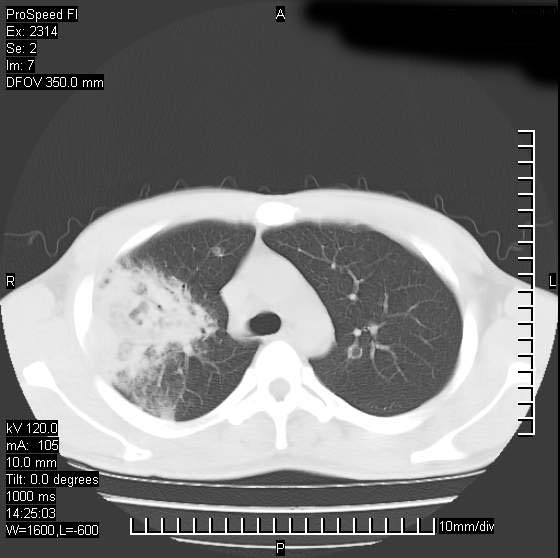

男性,再生障碍性贫血,入院前发热10天,最高40c,右侧胸痛,外院ct示右上,中肺边缘模糊的球性影(就是我现在图中标示的范围),考虑炎症,在我院使用头孢呋辛,洛美沙星10天,高烧消退,自感下午稍有发热,但今天ct示右上,中肺病灶明显扩大,还是考虑炎症,看其中的球型影是否霉菌感染??,是否能排除结核?

右肺中叶外侧段病变,上缘界限不清,下缘锐利,以段性发病为主,内见巨大空洞及空洞内容物,结合病史首先考虑:化脓性肺炎。不除外霉菌感染!

支持考虑真菌感染,内部密度低些,且与外壁有分离,不符合肺脓肿表现,但最好有前片对比,

片状高密度影内见空洞影,内可见球形软组织密度影,并有新月征,考虑霉菌感染.